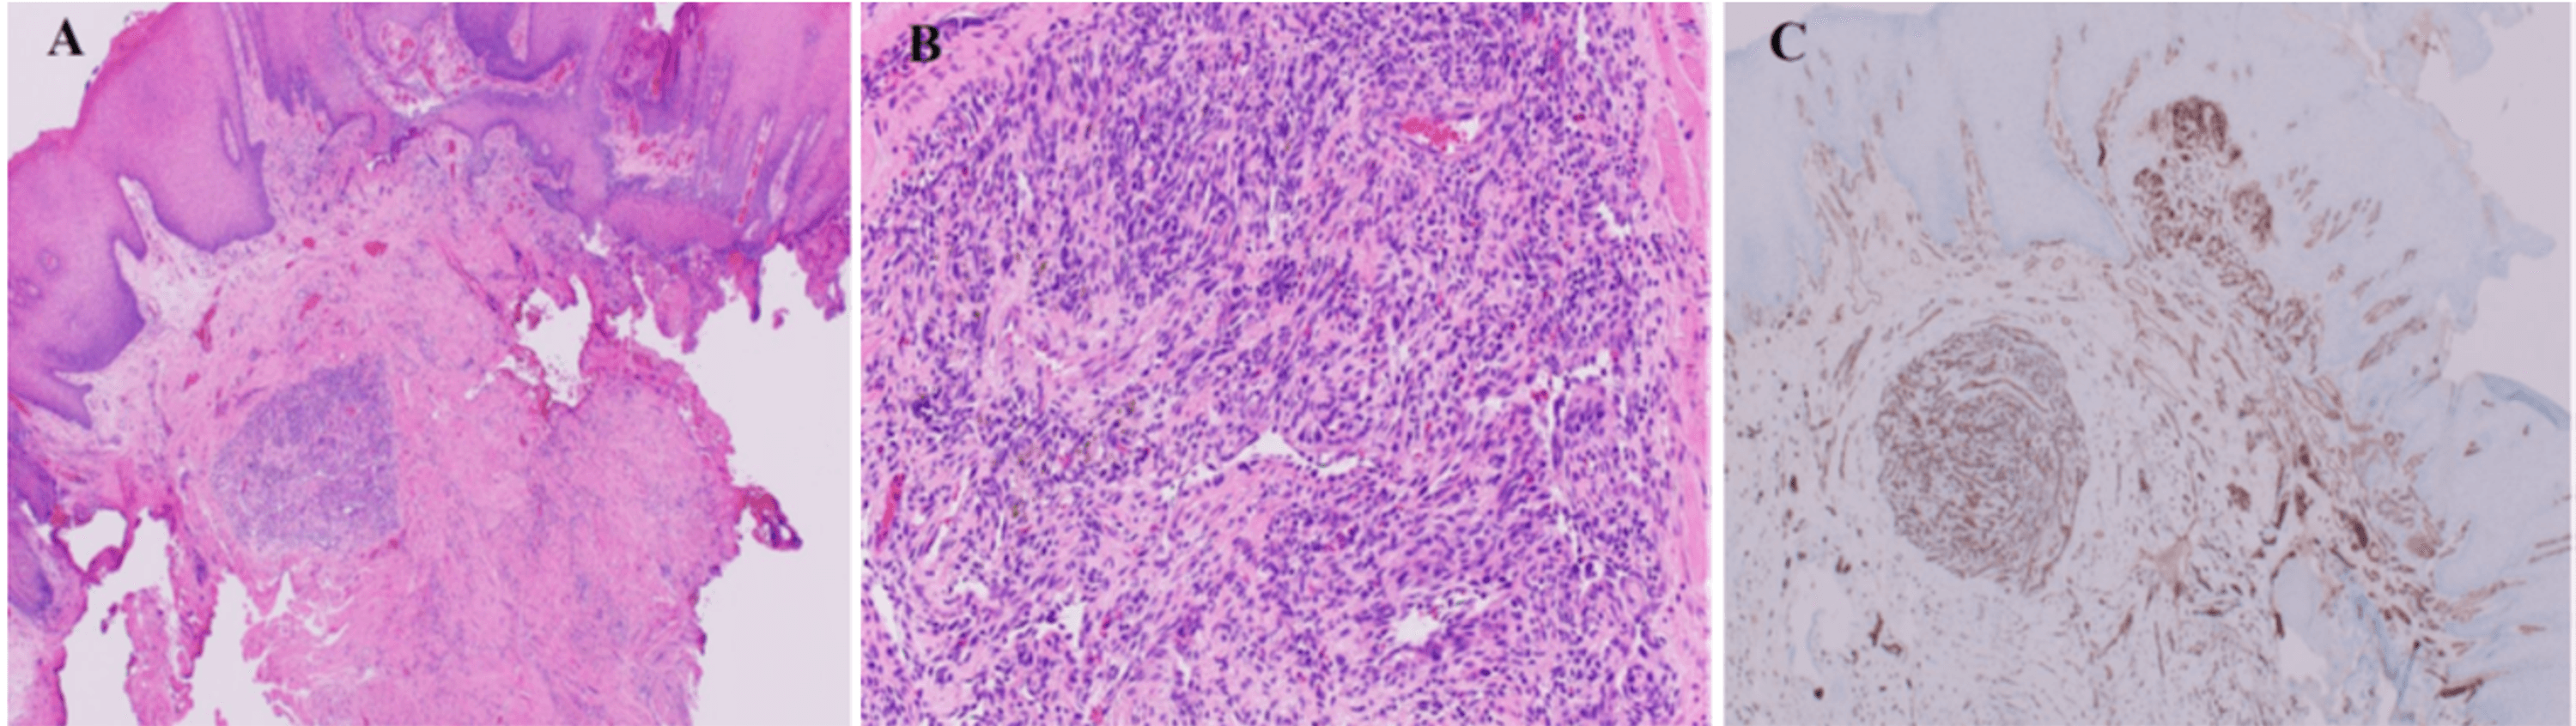

Oral Pyogenic Granuloma Histology Ada Code For Removal Of Pyogenic Granuloma Cpt code 17111 should be reported with one unit of service for removal of benign lesions other than skin tags or cutaneous. Pyogenic granuloma also known as lobular capillary hemangioma and granuloma teleangiectaticum, is a relatively common benign vascular tumor. Patient demographics total (n = 98)surgically managed (n = 63)topically managed (n = 35)p value ∗ female, n (%) 33. Ada Code For Removal Of Pyogenic Granuloma.

Oral Pyogenic Granuloma Histology vrogue.co Ada Code For Removal Of Pyogenic Granuloma It usually appears as a red, rapidly growing lesion. Explain the evaluation of pyogenic. Pyogenic granuloma also known as lobular capillary hemangioma and granuloma teleangiectaticum, is a relatively common benign vascular tumor. Patient demographics total (n = 98)surgically managed (n = 63)topically managed (n = 35)p value ∗ female, n (%) 33 (34%) 23 (37%) 10. Pyogenic granuloma (pg) or. Ada Code For Removal Of Pyogenic Granuloma.